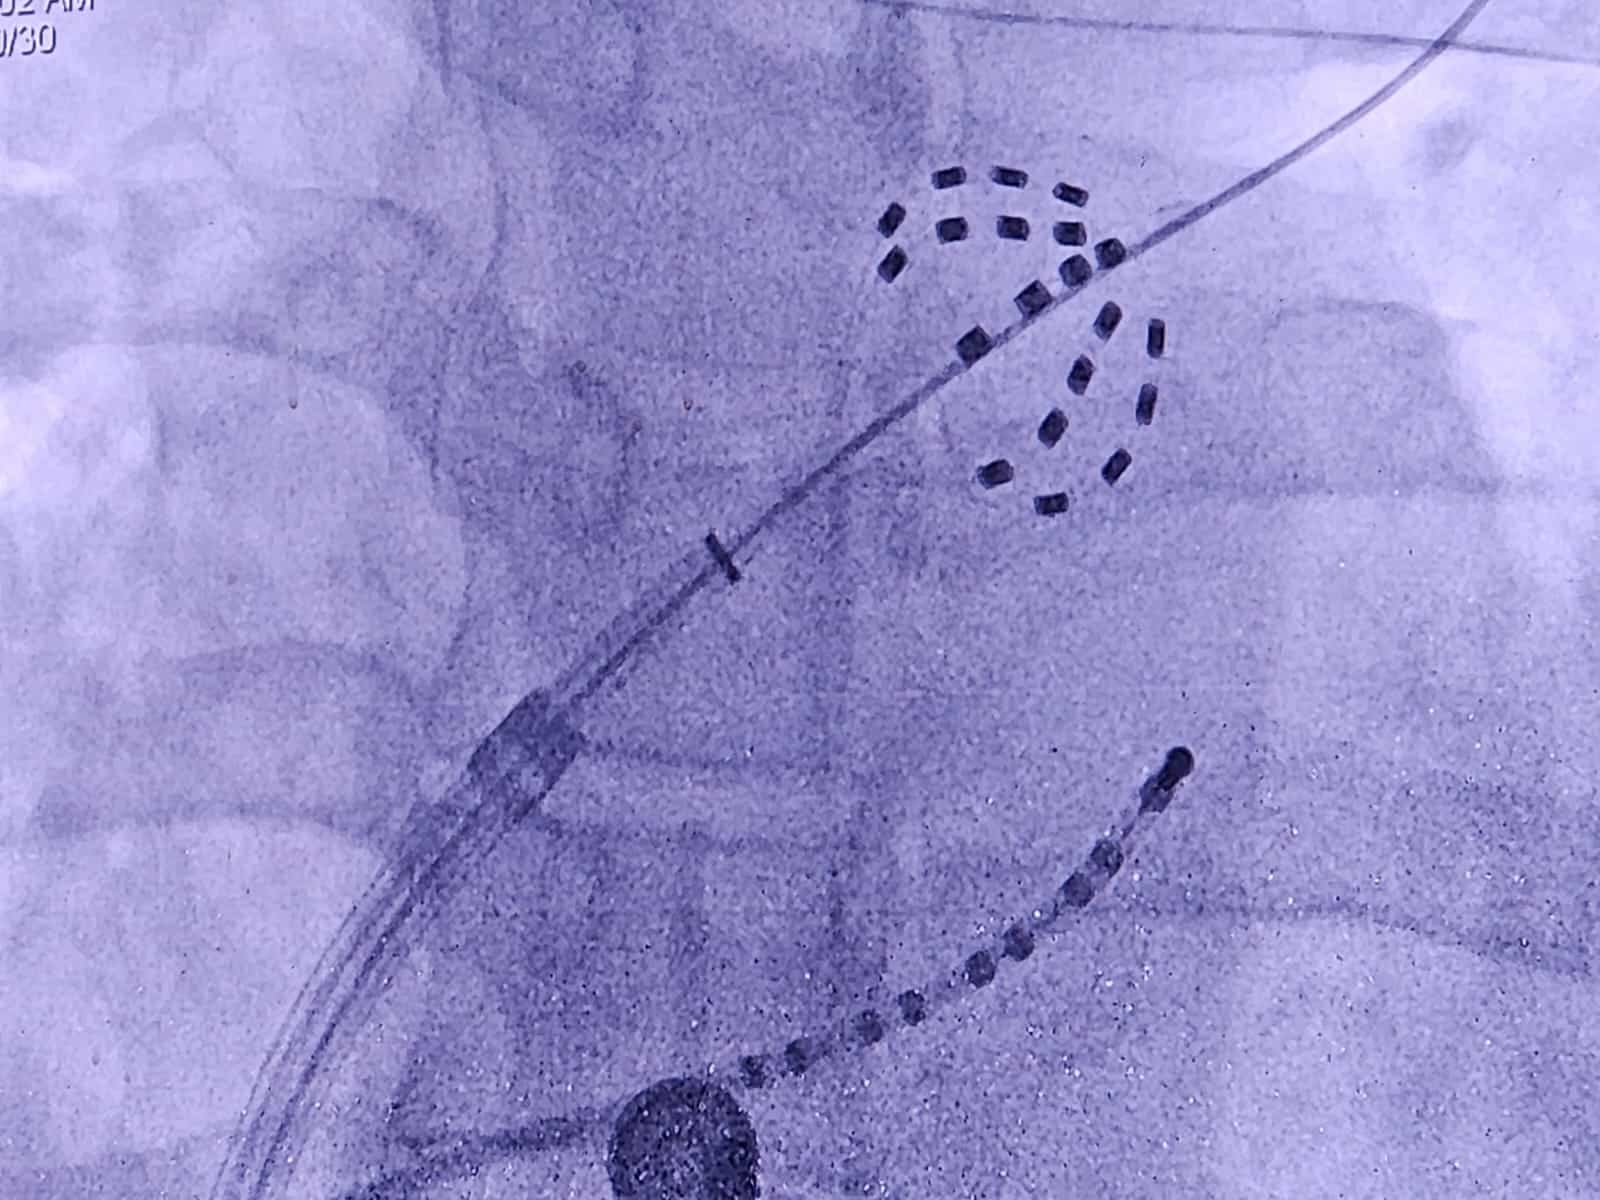

ووضّح الدكتور نجيب بن زهران الرواحي مدير المركز الوطني لطبّ وجراحة القلب لوكالة الأنباء العُمانية أنّ التقنية الجديدة تُعرف باسم “نبض المجال الكهرومغناطيسي” (Pulse Filed ablation)، وهي من أحدث التقنيات في العالم لعلاج اضطراب النبض الأذيني، وتتميز بالفعالية العالية وقِلة المضاعفات.

وبيّن أنّ هذه التقنية تهدف إلى وقف الاضطرابات الكهربائية في الأذينين، وهو ما يؤدي إلى عودة النبض إلى وضعه الطبيعي حيث تُجرى هذه العملية باستخدام قسطرة يتمُّ إدخالها إلى القلب من خلال الوريد الفخذي.